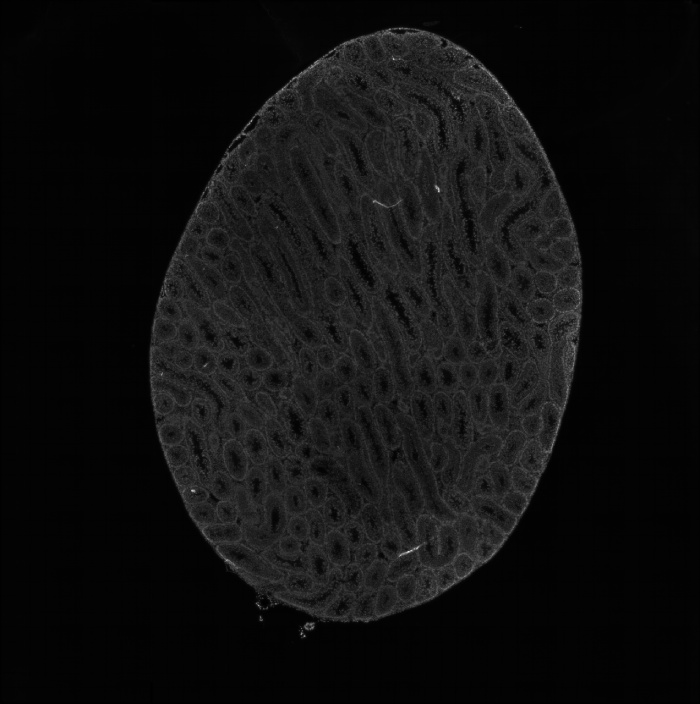

組織umi-count統(tǒng)計(jì)圖

圖2 組織UMI count統(tǒng)計(jì)圖